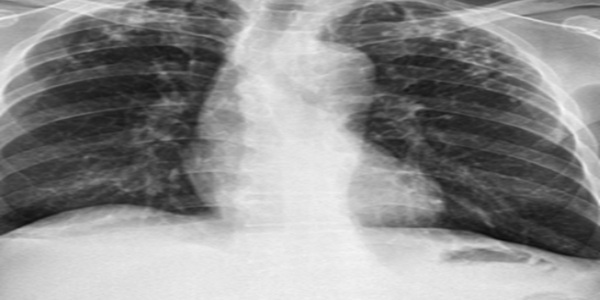

결핵은 폐결핵, 폐외결핵 등 다양한 형태로 나타날 수 있습니다. 폐결핵은 가장 흔한 형태의 결핵으로, 기침, 가래, 객혈 등의 호흡기 증상이 나타납니다. 기침은 초기에는 가벼운 기침으로 시작하지만, 점차 심해지고 2주 이상 지속될 수 있습니다. 가래는 맑은 가래에서 누런 가래로 변할 수 있으며, 피가 섞여 나오기도 합니다. 객혈은 기침과 함께 피가 나오는 증상으로, 결핵이 진행된 경우에 나타날 수 있습니다. 이 외에도 발열, 오한, 피로감, 식욕 부진, 체중 감소, 야간 발한 등의 전신 증상이 나타날 수 있습니다. 폐외결핵은 폐 이외의 장기에 발생하는 결핵으로, 림프절, 뼈, 관절, 뇌, 신장 등 다양한 장기에 발생할 수 있습니다. 폐외결핵의 증상은 발생 부위에 따라 다르지만, 발열, 통증, 부종 등의 증상이 나타날 수 있습니다. 결핵은 초기에는 증상이 없을 수 있으며, 증상이 나타나더라도 감기와 비슷하게 느껴질 수 있습니다. 따라서 2주 이상 기침, 가래 등의 호흡기 증상이 지속되거나, 발열, 피로감, 체중 감소 등의 전신 증상이 나타나면 결핵을 의심하고 병원에 방문하여 진료를 받아야 합니다. 결핵 진단은 흉부 X선 촬영, 객담 검사, 결핵균 검사 등을 통해 이루어집니다. 흉부 X선 촬영은 폐의 이상 여부를 확인하는 검사이며, 객담 검사는 가래 속에 결핵균이 있는지 확인하는 검사입니다. 결핵균 검사는 객담을 배양하여 결핵균을 확인하는 검사로, 가장 정확한 결핵 진단 방법입니다.